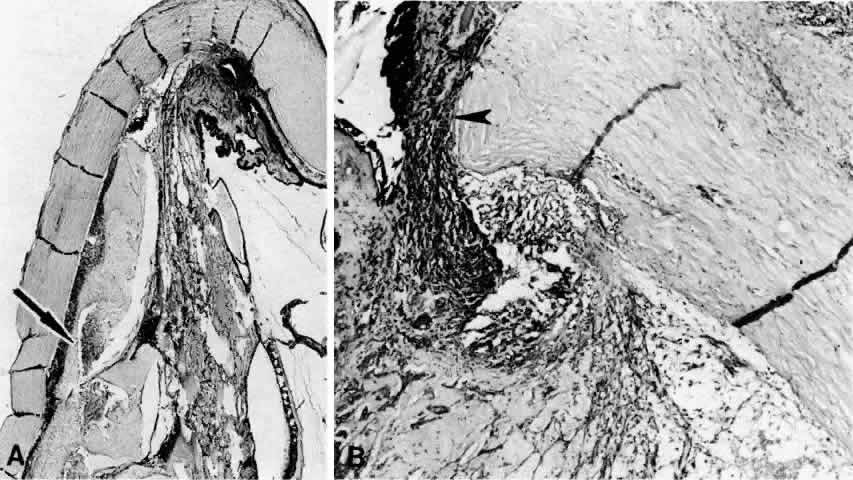

Fig. 20. A 61-year-old man presented with a 10-day history of decreasing vision in the left eye.96 Examination disclosed a vision of hand motions, an irregularly shallow anterior chamber, closure of the angle, and an intraocular pressure of 45 mmHg. The ora serrata was visible without scleral depression. Ophthalmoscopic examination disclosed two large areas of solid-appearing lesions of the pars plana and anterior choroid (situated superonasally and inferotemporally), detachment of the retina, and a diffuse pigmentary disturbance, which was linear in some areas. Transscleral transillumination disclosed that areas of solid choroidal lesions lit up when viewed through the pupil. Radioactive phosphorus uptake was 16% at 1 hour, 18% at 24 hours, and 44% at 72 hours. The eye was enucleated because of the suspicion of a malignant melanoma. A. An extensive ciliochoroidal effusion (asterisks) showing mild diffuse and marked focal (arrowhead) infiltration of lymphocytes. The equatorial sclera is markedly thickened, and there is a large serous detachment of the retina (H & E, × 17). B. Edematous choroid with a large aggregate of lymphocytes (H & E, × 100). C. The equatorial area shows a thickened sclera, an edematous choroid with diffuse and marked focal aggregates of lymphocytes, localized area of retinal pigment epithelial hypertrophy and hyperplasia (arrowheads), slight folds in the retinal pigment epithelium and inner aspect of the choroid (arrows), and proteinaceous material (asterisk) in the subretinal space (H & E, × 40). D. A choroidal effusion with overlying proliferation of retinal pigment epithelium in nodular and linear configurations. Proteinaceous material is present in some areas in or beneath the retinal pigment epithelium (arrowheads) (H & E, × 180).

Histopathologically, there is a variable lymphocytic infiltrate in the ciliary body and choroid (see Figs. 19 and 20; Fig. 21).96